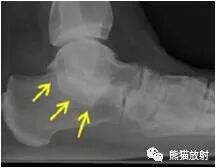

足正侧位平片

1、足侧位X线片上。

2、食蚁兽的鼻子:跟骨的前上部管状伸长,接近舟骨或与其重叠。

3、提示跟舟联合

跟舟联合在侧位X线片上呈现食蚁兽鼻征,拍摄45°内斜位X片观察跟舟联合